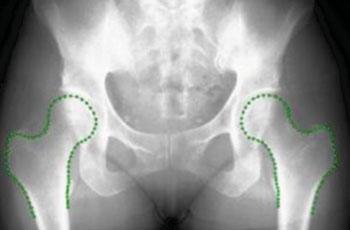

Una imagen del software Buscador de Huesos (Bone Finder) (Fotografía cortesía de la Universidad de Manchester). Hay escasez de radiólogos en el Reino Unido y, debido a la creciente necesidad de que los investigadores trabajen con grandes bases de datos de imágenes radiográficas, este software, desarrollado con financiación del Consejo de Investigación en Ingeniería y Ciencias Físicas del Reino Unido, ha sido diseñado para detectar automáticamente las formas de los huesos en las imágenes, en lugar de depender personalmente de los investigadores. Este sistema ya puede identificar las caderas. Sin embargo, los investigadores del Instituto de Salud de la Población de la Universidad de Manchester (Reino Unido) quieren modificarlo ahora para poder delinear las rodillas y las manos y así estar en capacidad de identificar otros huesos y estructuras internas del cuerpo. La financiación permitirá darle un mayor desarrollo, con lo cual se podrá llegar a asegurar que el sistema sea lo suficientemente exacto para utilizarlo en los hospitales con el fin de obtener un diagnóstico rápido de los problemas de los pacientes.

La financiación de 300.000 libras esterlinas dura tres años y se

basa en una investigación anterior que ayudó a desarrollar el

software, llamado Buscador de Huesos (Bonefinder), para

identificar los problemas y encontrar los contornos de las

caderas. Este software gratuito ha sido implementado por una serie

de grupos de investigación, entre ellos algunos con sede en Oxford

y en el estado norteamericano de California.